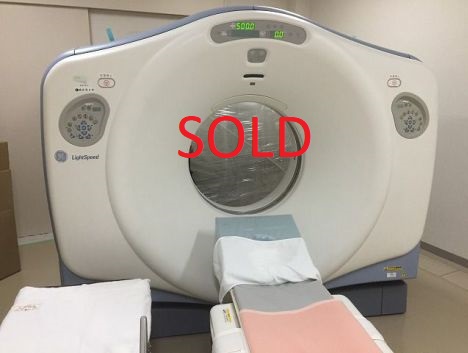

GE HP60 (2004)

HMS Stock Number: GE-16-0816-03

Manufacture: General Electric

Model: Lightspeed HP 60 XR-29 compliance

Year: 2004

Gantry Revolution: 792802

Gantry Type: H2

Tube Installed: Oct 2007

Tube Usage: 106 million mAs

Generator Type Jedi

Console Type: GOC 4

DAS Type: MDAS

Software: 07MW11.10_SP4-1-3 HP_P_M16_G_HPT

Software Options: Vari Viewer smart Prep Power 440 Patient -16-Slice 3000 Image Series

Smart Speed Helical Tilt 90KVA Direct-3D Connect Pro Volume Viewer

Comments: The System is in great condition and will be available in three weeks

REFURBISHED GE HP60 FEATURES

- Extreme Console

- 16 Slice

- Spiral Slices/Seconds on Tube: 140874

- Tube last replaced April 2009

- S/W Options: CTA, DICOM

- Good working condition and appearance

- Under Service Contract